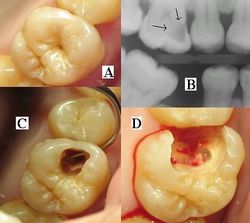

حدوث التسوس وتطوره

تقوم الحموض الناتجة من عملية تخمر السكاكر بحل العناصر المعدنية والعضوية التي تدخل في تركيب ميناء السن فتبدو المنطقة بيضاء طبشورية وذات ملمس خشن. ولدى تزايد إنتاج الحموض وعدم تطبيق الفلوريد الموضعي على الأسنان الذي يقوم عادة بإيقاف تطور التسوس، يتهدم الميناء وتصل الإصابة إلى العاج مشكلة حفرة التسوس التي يمكن ملاحظتها سريرياً ويبدأ الإحساس بالألم لدى التعرض إلى مؤثرات خارجية من سخونة وبرودة أو الضغط أثناء المضغ. عند إهمال معالجة التسوس في هذه المرحلة يزداد التخرب وتصل الإصابة إلى لب السن الذي يصاب بالالتهاب وترافقه موجات حادة من الألم وخاصة في أثناء الليل. إن عدم تطبيق المعالجة الملائمة في هذه المرحلة يؤدي إلى تموت اللب وإصابته بالتعفن وتتكون الخراجات الحادة والمزمنة والآفات الذروية التي تنتهي بقلع السن المصابة.

التشخيص